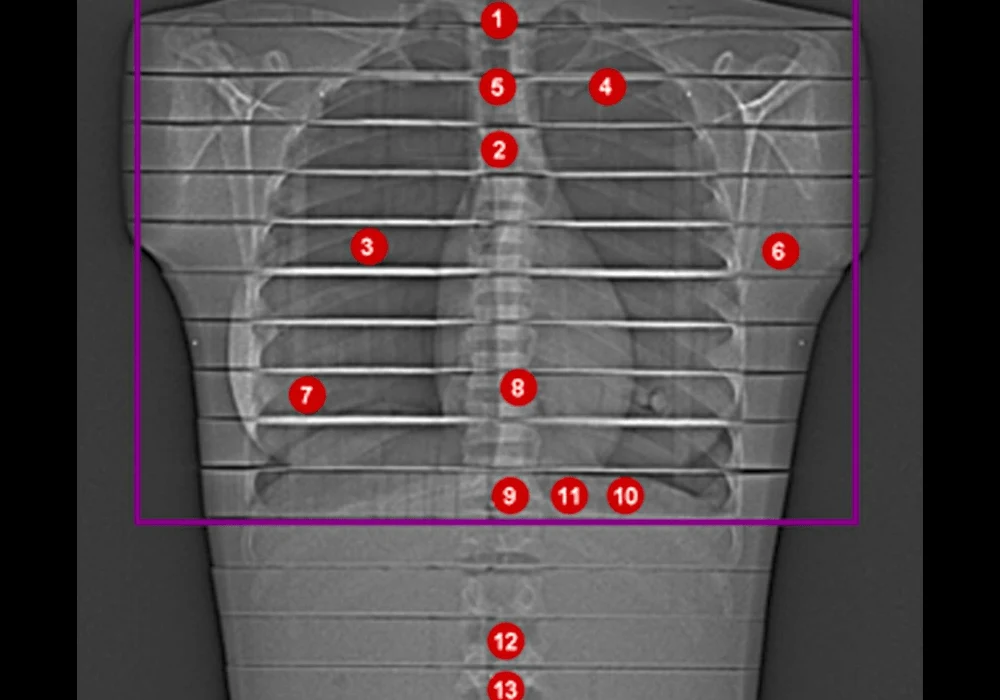

Traditional methods of estimating radiation exposure in CT imaging, such as using the dose-length product (DLP), often fail to provide an accurate picture of the actual dose absorbed by the patient. This study employed thermoluminescence dosimetry (TLD) to measure the radiation dose more precisely. TLD involves using thermoluminescent materials that record the absorbed radiation dose, which is later read out by heating the material and measuring the emitted light. This method provides a direct measurement of radiation exposure in specific organs, offering a more accurate assessment than DLP.

The study revealed a significant discrepancy between the radiation doses calculated from DLP and those measured using TLD. Specifically, the effective doses measured by TLD were between 131% and 170% higher than those calculated from DLP. This finding is crucial, as it suggests that the conventional approach to estimating patient radiation exposure may significantly underestimate the actual dose, potentially leading to an underappreciation of the risks associated with CT imaging. By contrast, TLD offers a more reliable and individualised measure of radiation exposure, particularly in studies involving advanced imaging technologies like PCD-CT.

This accurate dose measurement is critical in lung imaging due to the sensitivity of thoracic organs to radiation. The use of TLD in this study highlights the need for more precise dosimetry methods in clinical practice, ensuring that the benefits of advanced imaging technologies are not overshadowed by underestimated radiation risks.